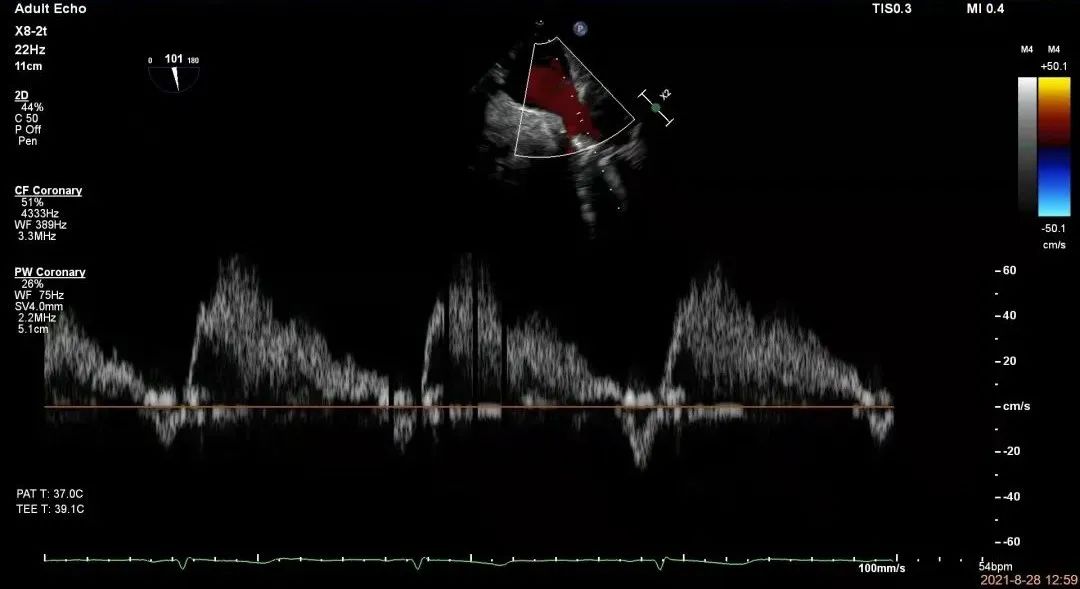

术后超声心动图

术后肺静脉血流